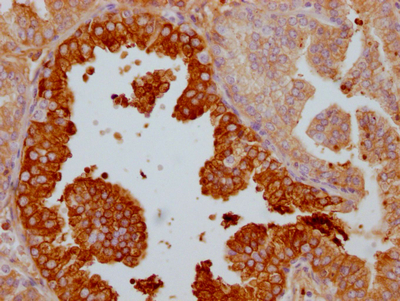

IHC image of CSB-RA697089A0HU diluted at 1:100 and staining in paraffin-embedded human prostate cancer performed on a Leica BondTM system. After dewaxing and hydration, antigen retrieval was mediated by high pressure in a citrate buffer (pH 6.0). Section was blocked with 10% normal goat serum 30min at RT. Then primary antibody (1% BSA) was incubated at 4℃ overnight. The primary is detected by a Goat anti-rabbit IgG polymer labeled by HRP and visualized using 0.05% DAB.